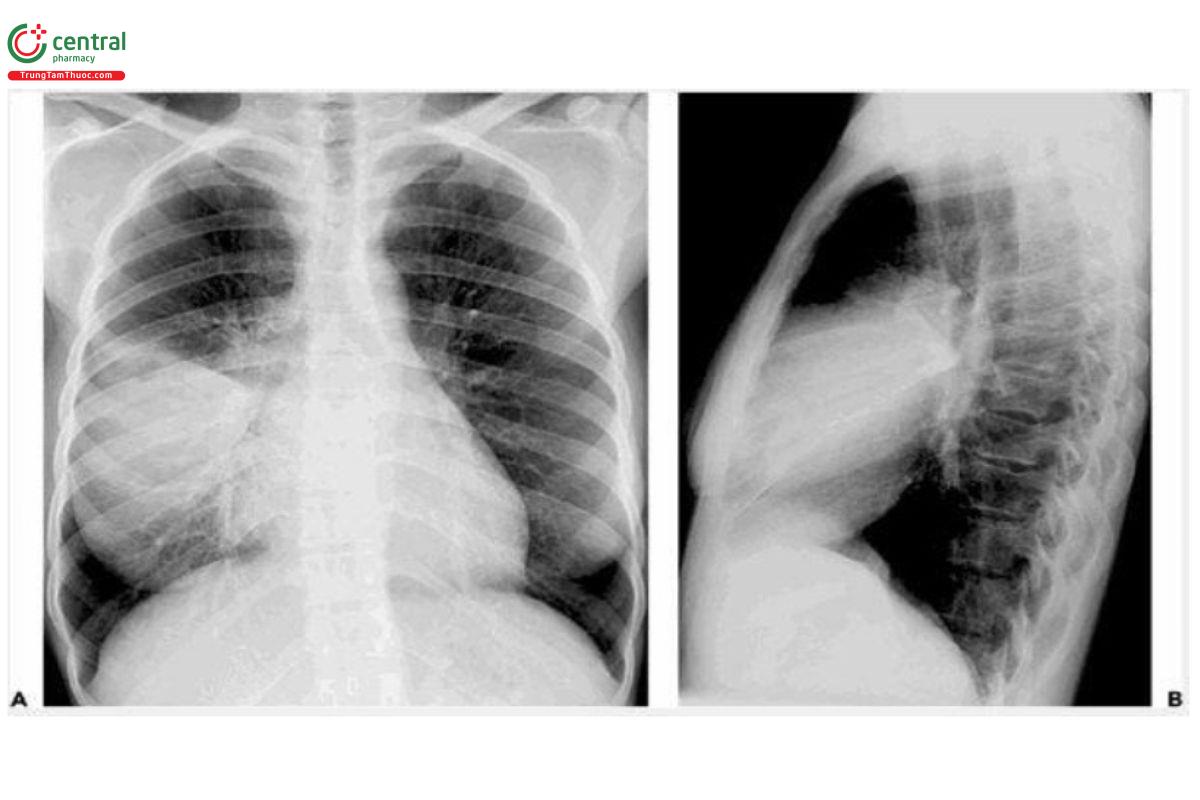

Tổn thương đông đặc chiếm ưu thế (viêm phổi phế nang/ thùy): khi đông đặc toàn bộ thùy phổi, được gọi là "viêm phổi thùy". Sự đông đặc này được hình thành do sự lan truyền của tình trạng viêm qua các lỗ Kohn hoặc các ống Lambert ở ngoại vi của phổi. Tuy nhiên quá trình đông đặc không theo phân thùy ở giai đoạn đầu của bệnh [6]. Hầu hết các viêm phổi do vi khuẩn như Streptococcus pneumoniae và Klebsiella pneumoniae xuất hiện đông đặc chiếm ưu thế.

Viêm phổi do Streptococcus pneumoniae: Hình ảnh tổn thương là viêm phổi phế nang/thùy, thường có hình ảnh phế quản hơi, không thay đổi kích thước vùng phổi đông đặc và không có hang. Thùy dưới thường gặp nhiều hơn và có thể xuất hiện ở nhiều thùy. Tổn thương hai bên gặp ở khoảng một nửa số bệnh nhân.